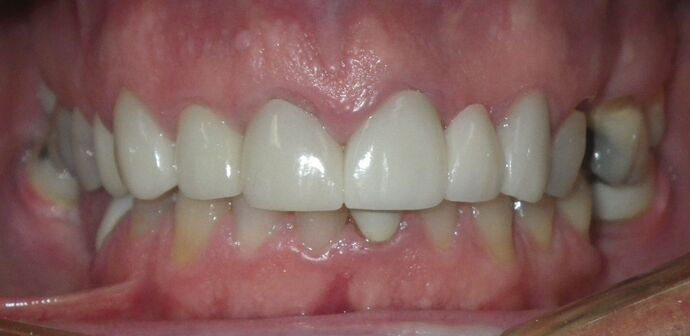

Cosmetic Changes with Veneers and Crown and Bridge: Case 5

Patient wanted to see about getting his upper front crowns replaced. He has had them for 35 plus years. Also concerns about his gums receding and the metal margins of crowns showing. Also talked with him about the need for crown lengthening which would have helped decrease the gummy smile; however, he chose not to do this. I thought just replacing the existing crowns to the existing gingival margins would be a great help. So the existing porcelain/metal crowns were removed and new all ceramic single unit crowns placed from upper right cuspid,lateral incisor and right central incisor. Then a 3-unit all ceramic bridge was placed from upper left central incisor to upper left cuspid. This patient and most of all his wife were very pleased with the end result.